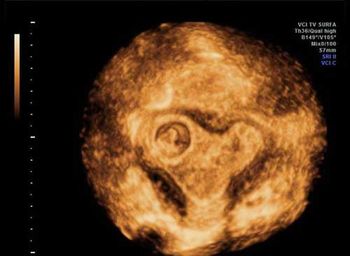

Challenge your anatomy knowledge; what body part is this 3-D image showing?